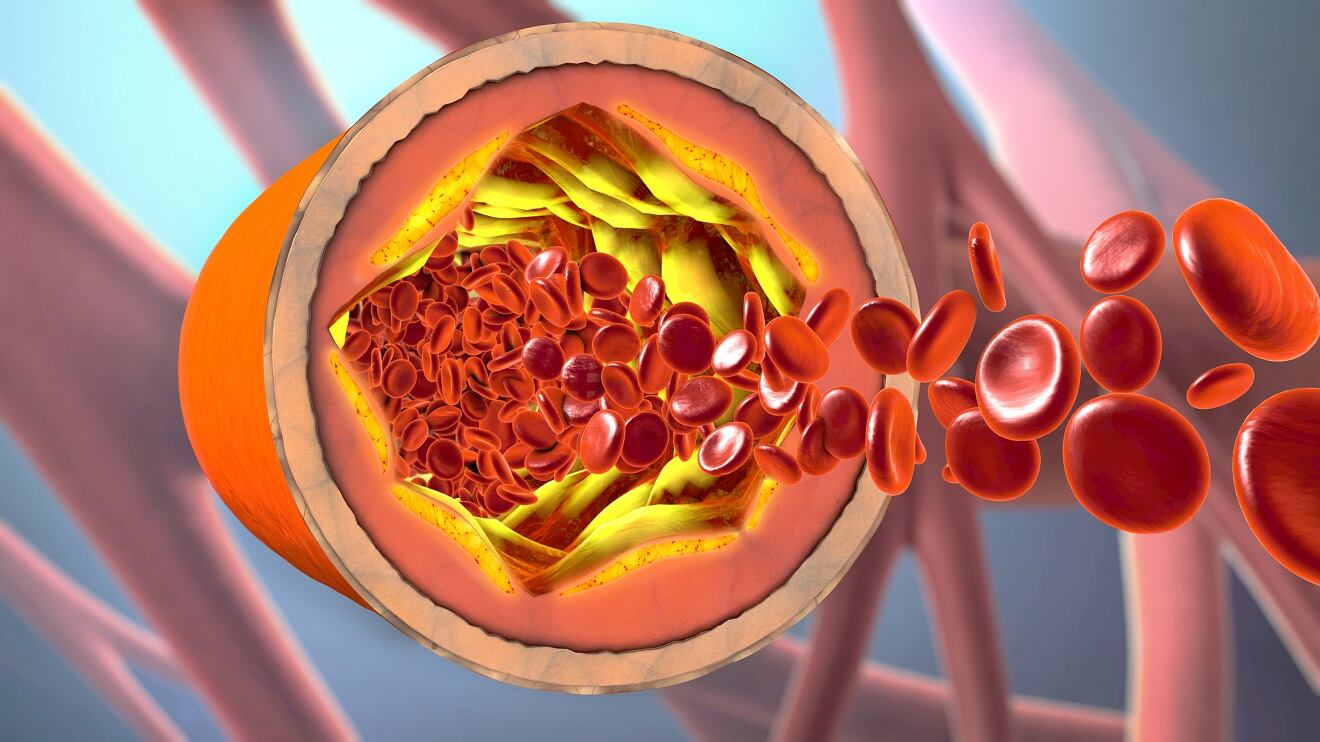

Los altos niveles de colesterol en sangre incrementan el peligro de enfermedades cardíacas, un factor relacionado con el derrame cerebral. La formación de placa en las arterias, derivada de altos niveles de colesterol, puede obstruir el flujo sanguíneo hacia el cerebro, desencadenando un derrame. Para comprender cómo estos procesos se desencadenan, es esencial conocer las lipoproteínas, transportadoras clave del colesterol en nuestro sistema.

La lipoproteína de baja densidad (LDL), a menudo etiquetada como “colesterol malo”, transporta el colesterol hacia la sangre y los tejidos, facilitando su acumulación en las arterias. Según Medical News Today, esta placa formada puede eventualmente bloquear arterias cruciales, dando lugar a un derrame cerebral. Por otro lado, la lipoproteína de alta densidad (HDL), conocida como “colesterol bueno”, actúa llevando el colesterol desde los tejidos hasta el hígado, donde es eliminado. Un nivel bajo de HDL puede aumentar el riesgo de derrame cerebral y enfermedad cardíaca.